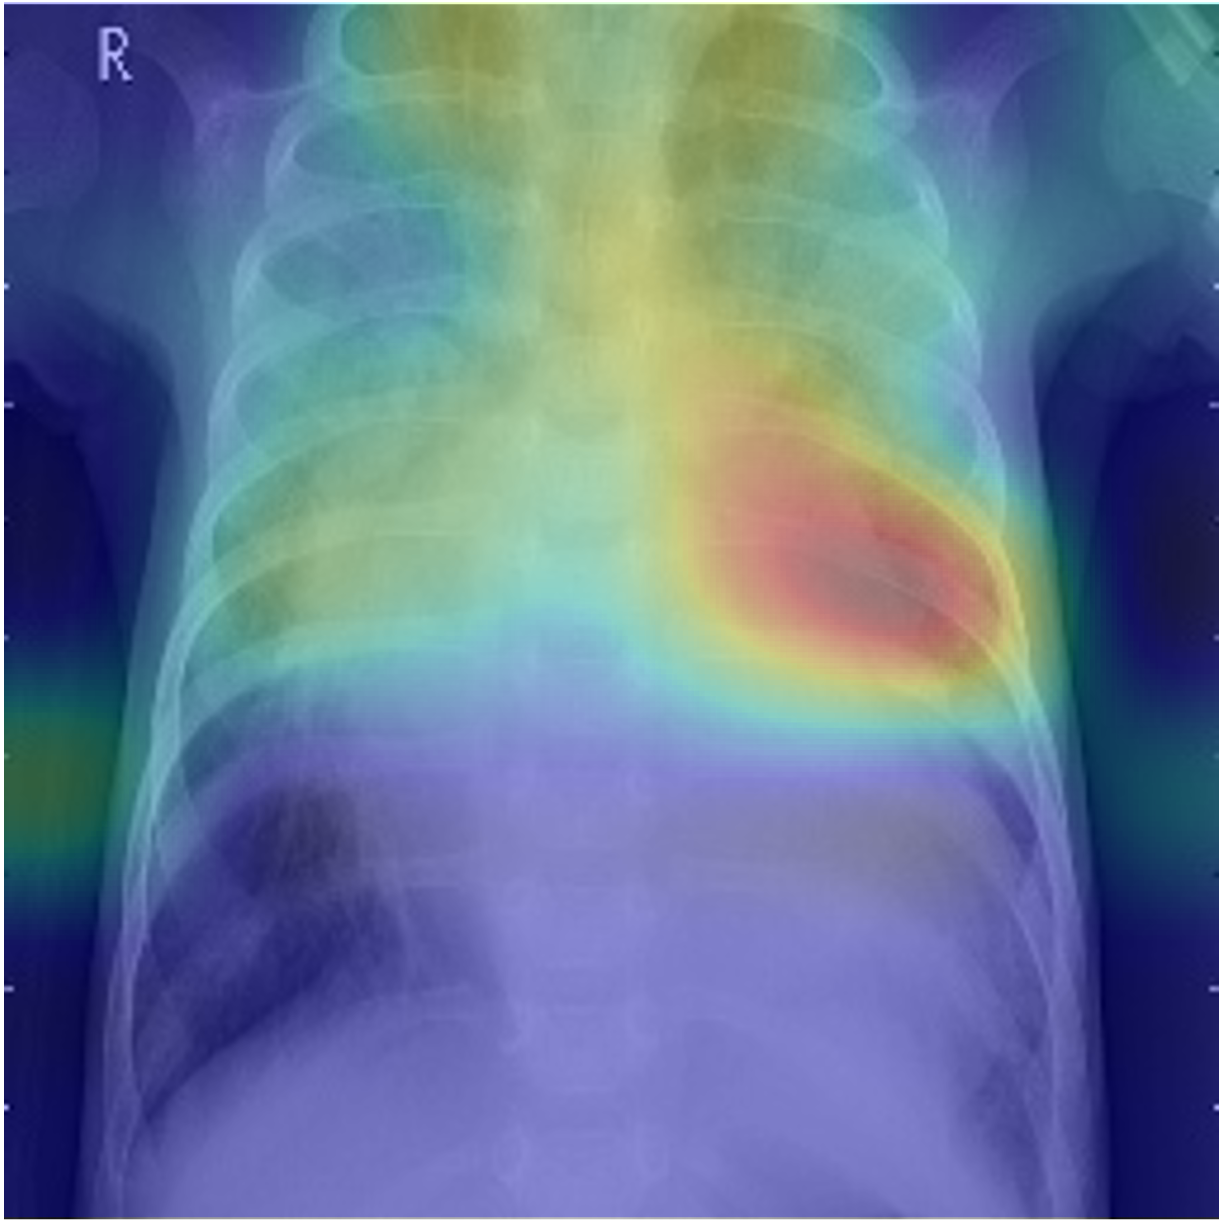

The impact of position guidance is visualized through the Class Activation Mapping (CAM) in Fig. 3. In the first row, the entire lung view fails to detect anomalies in the left region. However, specific views focused on the left, upper, and lower sections of the lung successfully identify these anomalies. In the second row, the left lung view detects anomalies that are missed in the entire lung view. These outcomes indicate the importance of utilizing diverse position prompts.